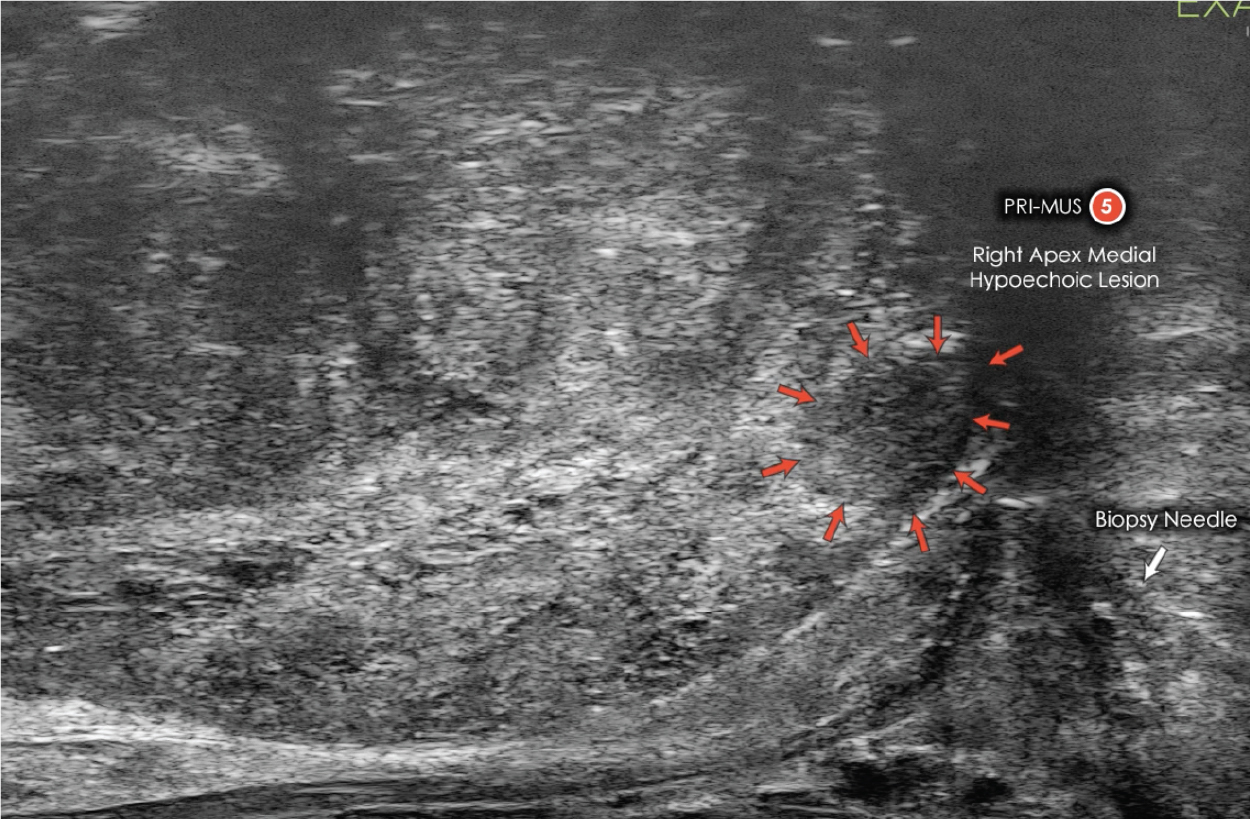

Differentiate Suspicious Regions assisted by the PRI-MUS evidence-based scale.

assisted by the PRI-MUS evidence-based scale.

Target in real-time

Urologists visualize suspicious regions and target biopsies with micro-ultrasound.